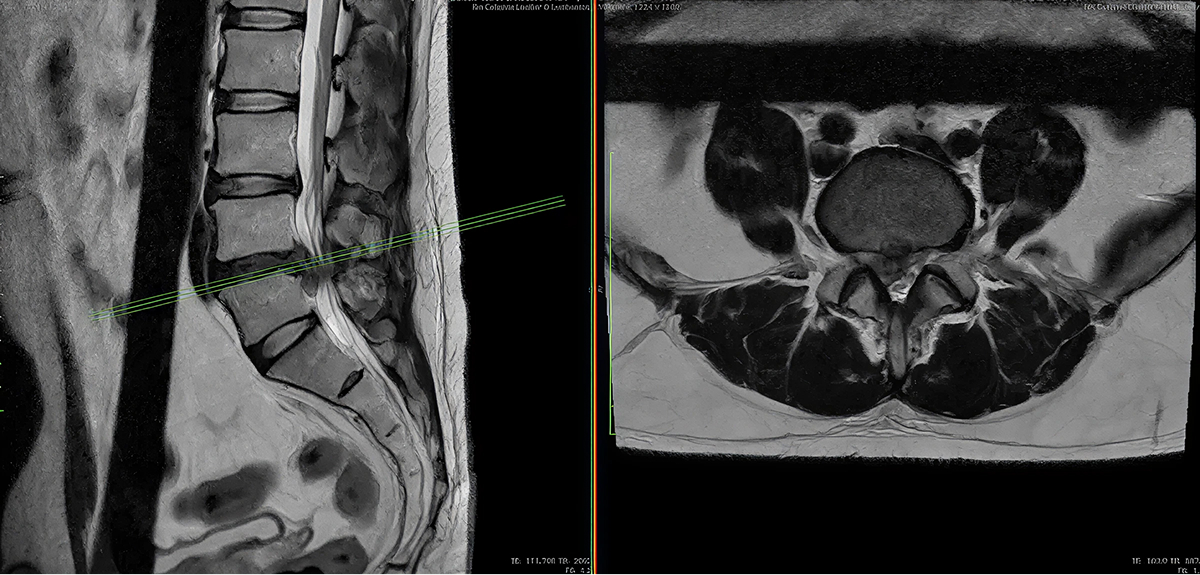

- Diagnóstico de vanguardia: empleamos imagen de alta resolución (resonancia magnética, tomografía), estudios neurofisiológicos y análisis clínico multidisciplinario para establecer el plan óptimo.

- Diagnóstico preciso: mediante resonancia magnética, tomografía, estudios de conducción nerviosa y valoración clínica por nuestro equipo multidisciplinario.

- Tratamiento conservador vs. quirúrgico: evaluamos primero las terapias no quirúrgicas (fisioterapia, infiltraciones, etc.). En caso de indicarse cirugía, empleamos técnicas modernas de mínima invasión, microcirugía e instrumentación vertebral para aliviar los síntomas y restituir la función.

- Cirugía especializada: nuestra experiencia en cirugía de columna lumbar incluye abordajes de mínima invasión (cirugía endoscópica), fusión vertebral, descompresión de raíces nerviosas, así como reparación de inestabilidad vertebral. Estas técnicas de mínima invasión permiten preservar de mejor forma la musculatura lumbar y acortar la recuperación del paciente en el posoperatorio.